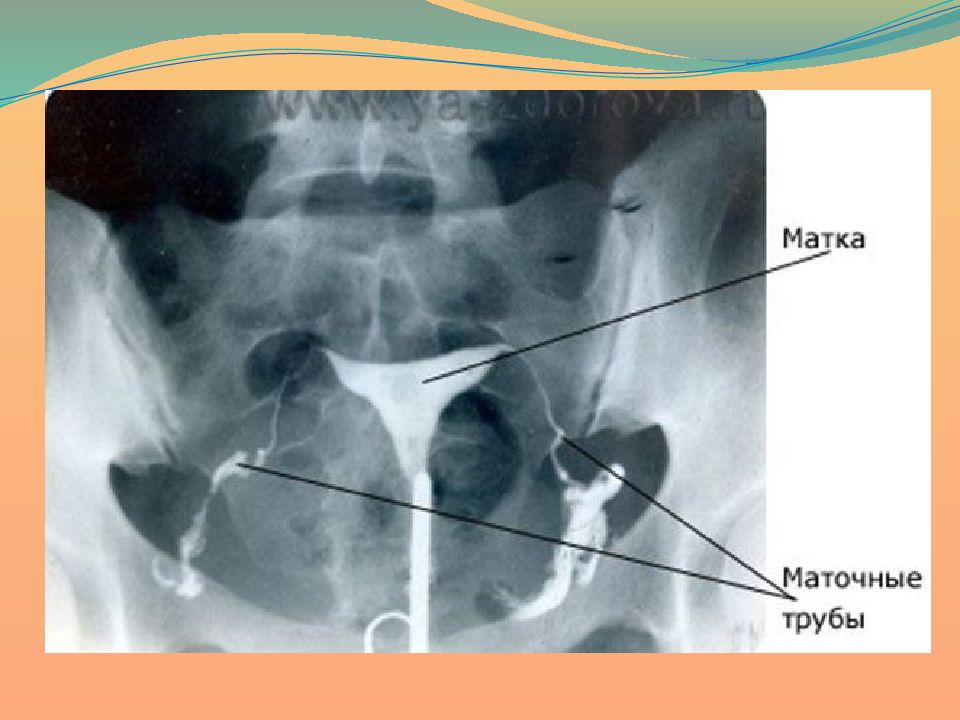

Гистеросальпингография: описание и фотографии